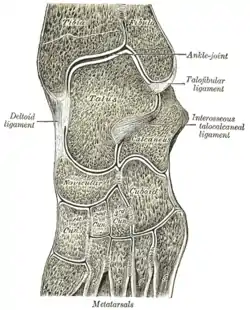

Skeleton of left foot. Medial aspect. Oblique section of left intertarsal and tarsometatarsal articulations, showing the synovial cavities.

Oblique section of left intertarsal and tarsometatarsal articulations, showing the synovial cavities. Ankle and tarsometarsal joints, showing bones of foot. Deep dissection.